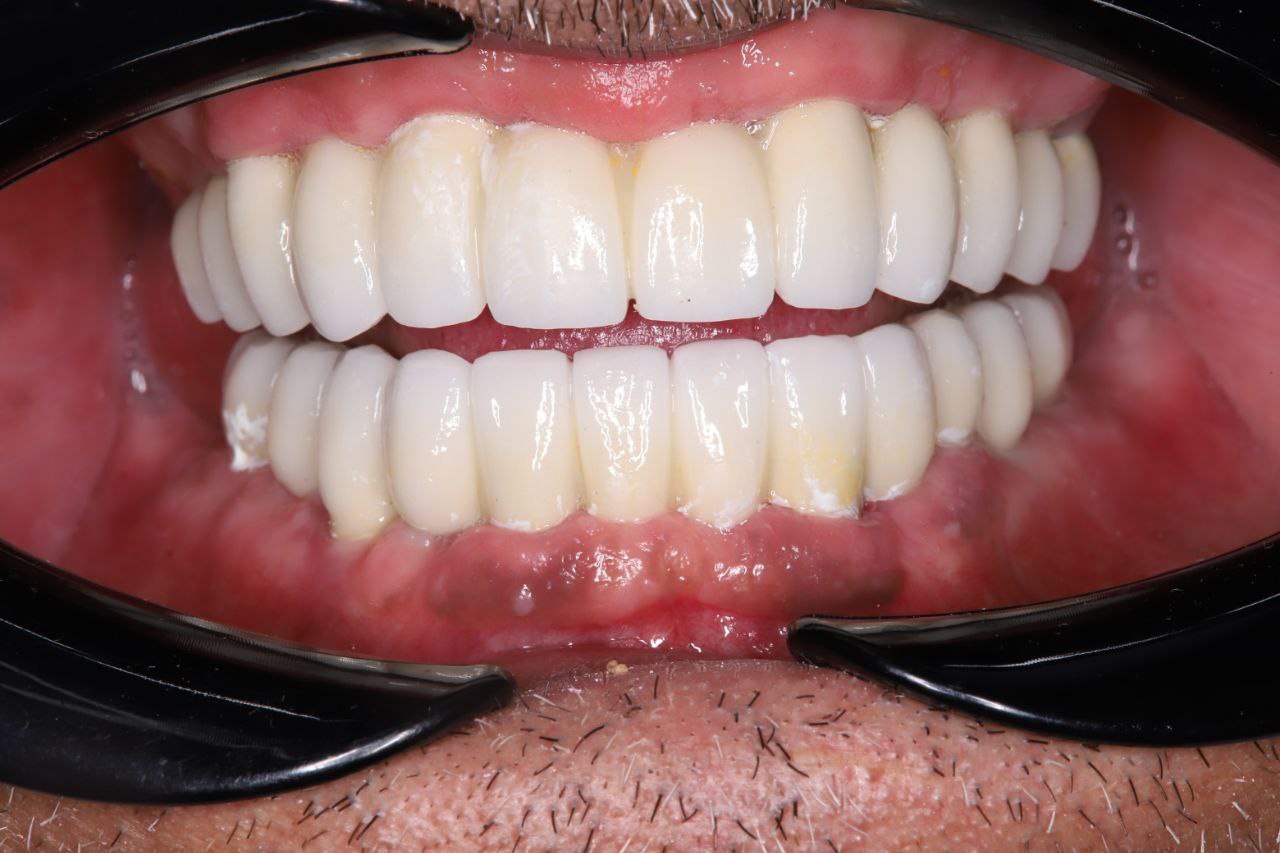

Результат проделанной работы

Пациент обратился с полным отсутствием зубов.

Проведена компьютерная диагностика и цифровое планирование лечения. Принято решение о восстановлении зубного ряда с опорой на импланты.

Установлено 6 дентальных имплантов. После хирургического этапа были изготовлены и зафиксированы временные коронки (временная ортопедическая конструкция) на период приживления имплантов. После завершения остеоинтеграции изготовлены и установлены постоянные коронки из диоксида циркония.

Результат — восстановлены функция жевания и эстетика улыбки.